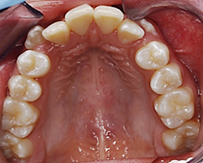

Al analizar las fotografías intraorales revelaron lo siguiente (Figura 2): Fotografía frontal: líneas medias dentales no coincidentes la inferior se encuentra con una desviación de 2 mm hacia la derecha, mordida abierta y caninos superiores ectópicos. (A). Fotografía lateral derecha (B) e izquierda (C): Clase II molar, clase canina no aplica debido a que los caninos no se encuentran en el arco.

Fotografía oclusal superior: Forma de arcada ovoide, apiñamiento en el sector anterior, palatinización de las piezas 1.2 y 2.2, piezas 1.3 y 2.3 ectópicas, paladar profundo (D). Fotografía oclusal inferior: Forma de arcada oval, lingualización de las piezas 4.5 y 4.6, ausencia de la pieza 3.7 (E). Fotografía de resalte: La sobremordida horizontal y vertical de -2 mm (F).